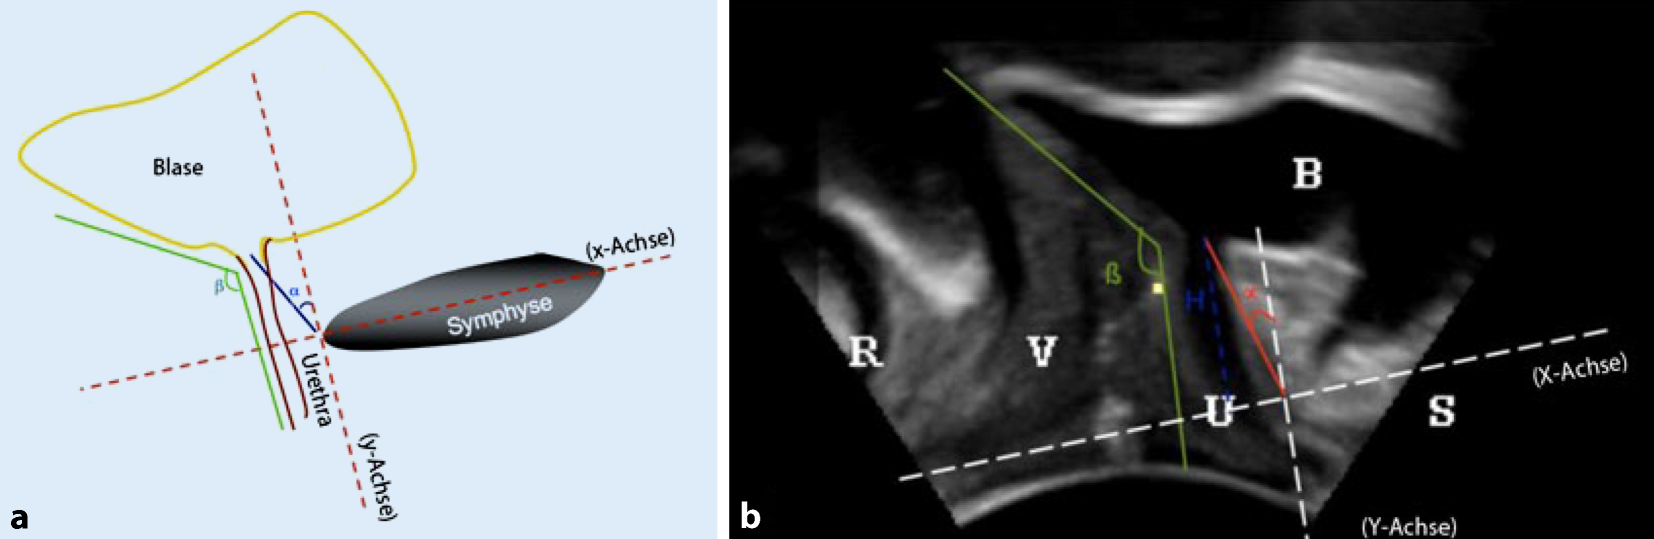

Ein weiteres Instrument zur Befundobjektivierung ist die perineale, vaginale oder Introitussonographie, die besonders bei Komorbiditäten im Beckenboden (Senkung, Voroperationen, Bestrahlung) in jedem Fall eingesetzt werden sollte (Abb. 1). Die Beurteilung der Anatomie, Lagebeziehungen und Beweglichkeit der Beckenorgane setzt eine entsprechende Schulung voraus. Eine weitere (radiologische) Bildgebung erübrigt sich damit in der Regel und bleibt speziellen Fällen vorbehalten [6].

Abb. 1

a Schemadarstellung der Beckenbodenkoordinaten bei der Frau, b Anwendung des Koordinatensystems auf ein Ultraschallbild bei der Frau, R Rektum, V Vagina, U Urethra, B Blase, S Symphyse. (Nachdruck mit Genehmigung aus: [6] ©Springer-Verlag Berlin Heidelberg 2015. Diese Abbildung fällt nicht unter die Creative Commons CC BY-Lizenz dieser Publikation)